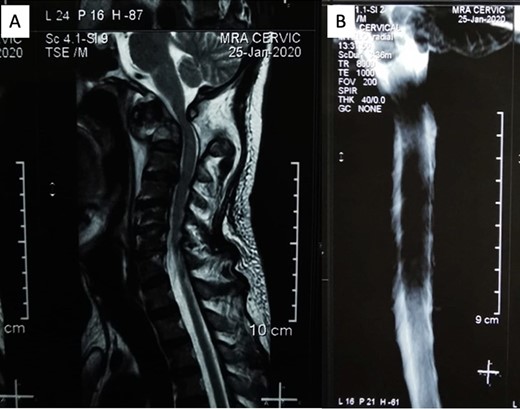

The patient reported sensory disturbances in all four extremities, particularly related to abnormalities in light touch, without any other sensory qualities being affected. A Cervical CT scan revealed a type III odontoid fracture, D’Alonzo type III, with atlantoaxial dislocation, fielding grade 3, and ossification of the posterior longitudinal ligament on the C4-C6 levels (Fig. 1). Cervical MR imaging showed cervical canal stenosis at the C1-C2 level due to atlantoaxial dislocation (Fig. 2). Consequently, we planned to proceed with stabilization surgery. We were unable to perform angiography on this patient due to limited facility resources for such examinations.

(A) Sagittal MRI showed significant compression on the occipitocervical junction due to atlantoaxial dislocation with blockage from (B) MR myelography.